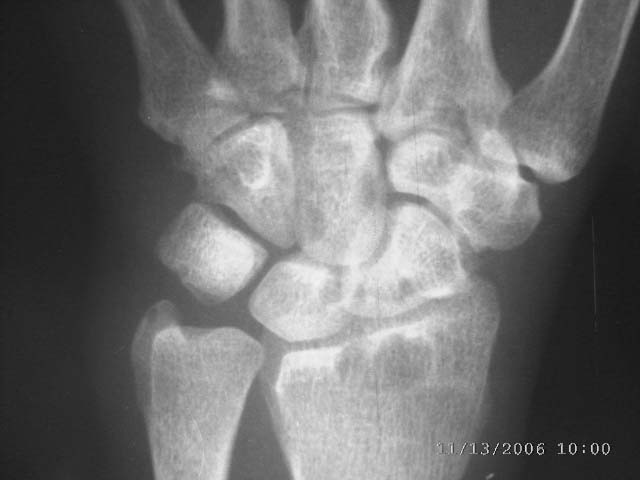

女45,右腕部夜间痛,晨僵感,局部皮温高,尺骨茎宊处轻度软组织肿胀2年余。自小感觉右手温觉和痛觉差。

右桡骨下端、舟骨,月骨,三角骨,头状骨,尺骨茎突均可见囊状低密度影,尺侧软组织似稍肿胀。患者虽然为女45,右腕部夜间痛,晨僵感,局部皮温高,尺骨茎宊处轻度软组织肿胀2年余。但类风湿似乎不象,我认为应考虑结核。

右桡骨下端、舟骨,月骨,三角骨,头状骨,尺骨茎突均可见囊状低密度影,尺侧软组织似稍肿胀。患者虽然为女45,右腕部夜间痛,晨僵感,局部皮温高,尺骨茎宊处轻度软组织肿胀2年余。我认为应考虑结核。(依据可见吻状破坏),自小感觉右手温觉和痛觉差,症状像神经性骨关节病,但影像不像。